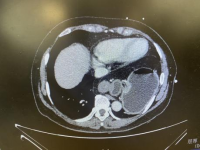

夏阳副主任医师在完善影像学检查发现,张女士所患为Ⅳ型食管裂孔疝,2/3的胃体从腹腔原来的位置通过膈肌食管裂孔钻入胸部后纵膈,并且发生胃扭转,同时还有部分结肠、网膜组织也都随胃的上移一并疝入。24小时测酸显示合并严重的反酸,并且由于长期的胃移位扭转,导致张女士进食困难、营养不良合并严重贫血。

由于病程时间长,疝内容物体积大且与周围毗邻的胸膜、后纵膈组织及膈肌脚黏连严重,疝囊顶部位置接近心脏心包后方及胸腔内大血管,稍有不慎会造成严重后果危机生命。这些都为手术制造了不少难度和挑战。由于左侧肺因为被巨大的疝内容物压迫超过60%,患者肺功能也受到一定的影响,对麻醉的实施也提出了很高的要求。8月30日,夏阳副主任医师团队在麻醉科倪文宗副主任医师的积极配合下,应用腹腔镜微创技术,经腹部五个小孔,通过扩大的食管裂孔进入胸部后纵膈,在有限的空间实施组织分离,精密解剖,将严重黏连、疝入的胃和结肠、网膜回纳至正常解剖位置,同时把胃底进行360度折叠包绕住松弛的食管下段,一并解决了胃食管反流问题。手术耗时1小时20分钟,术中出血小于10ml,术后第二天张女士即可下地活动,进食流质,第三天即康复出院。